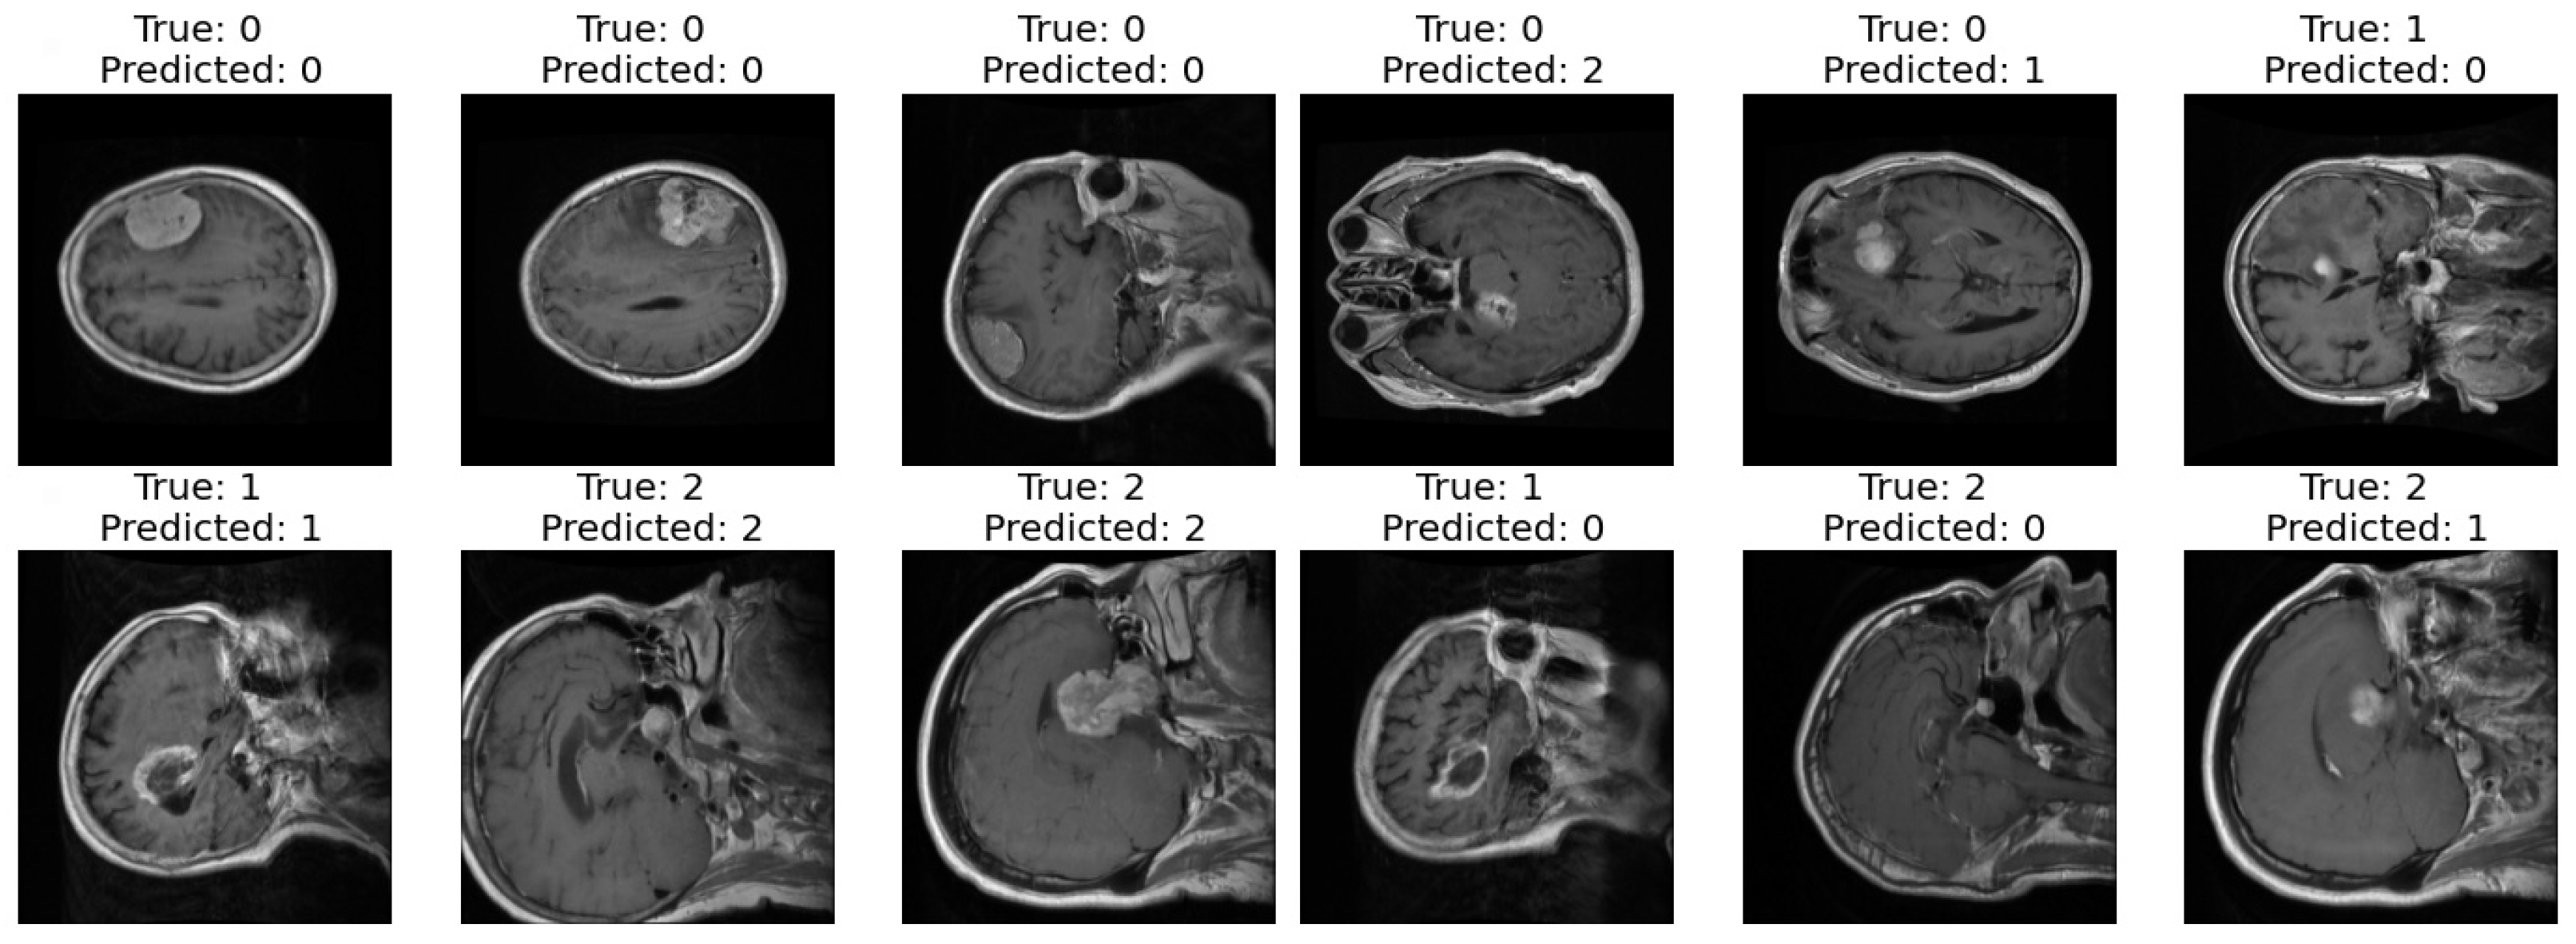

- Predicted Class: Simultaneously, the classification branch assigns a ‘Predicted Class’ to the scan. The labels, denoted by integers (0, 1, 2), classify the scan into categories that reflect the model’s interpretation of the underlying pathology.

3.2. First Dataset (Classification Task)

3.3. Second Dataset (Classification and Segmentation Task)